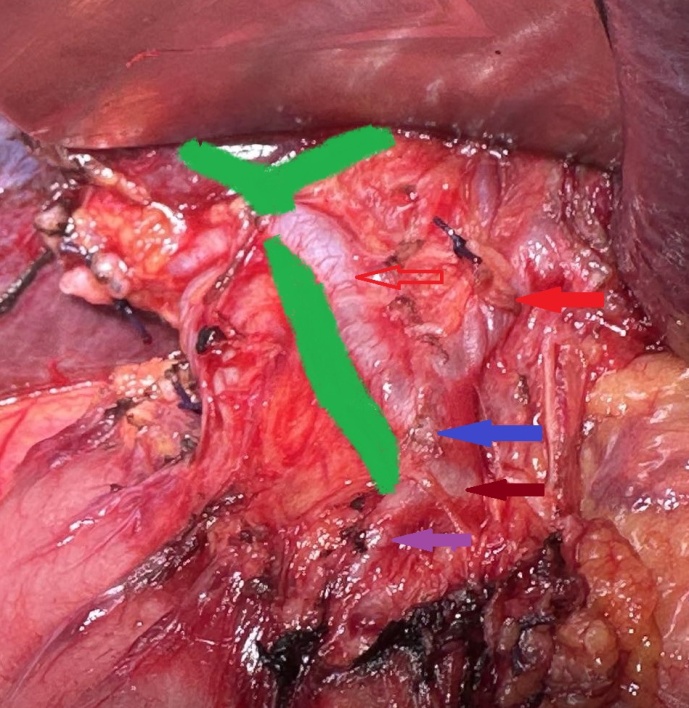

Compression of the common hepatic duct by the right hepatic artery is evident. Red arrows: right and left hepatic artery. Blue arrow: proper hepatic artery. Brown arrow: common hepatic artery. Purple arrow: gastroduodenal artery (Courtesy Dr. V. Penopoulos).